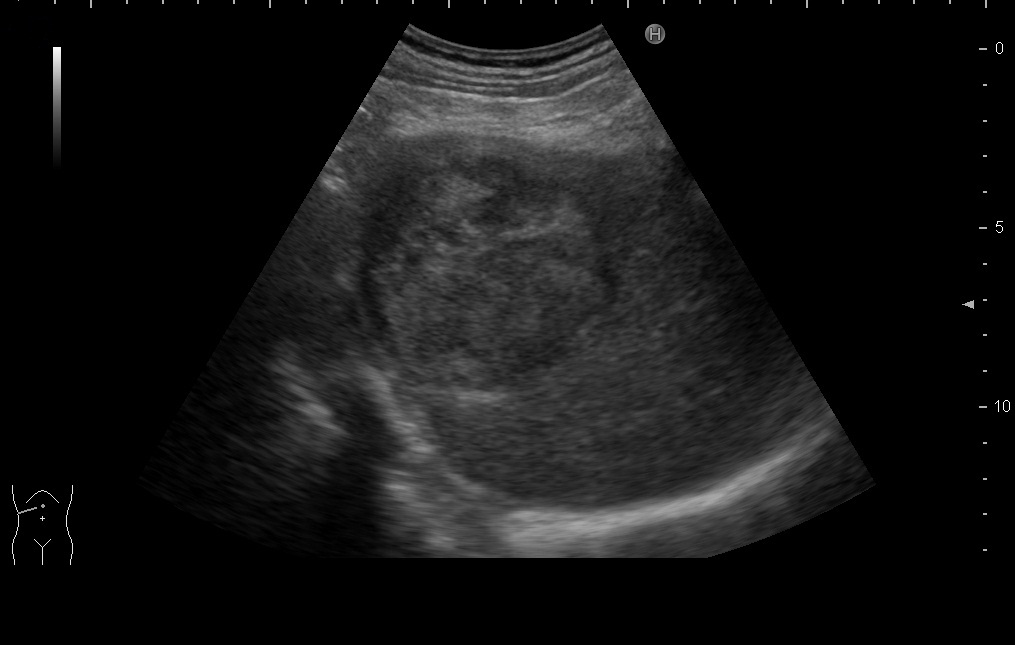

腹部超音波検査

肝臓、胆嚢、膵臓、腎臓、脾臓、大動脈、消化管、骨盤腔内を描出し、臓器の大きさや形態、実質を観察します。腫瘤があれば良悪性の鑑別をしたり、周囲の変化などを観察します。